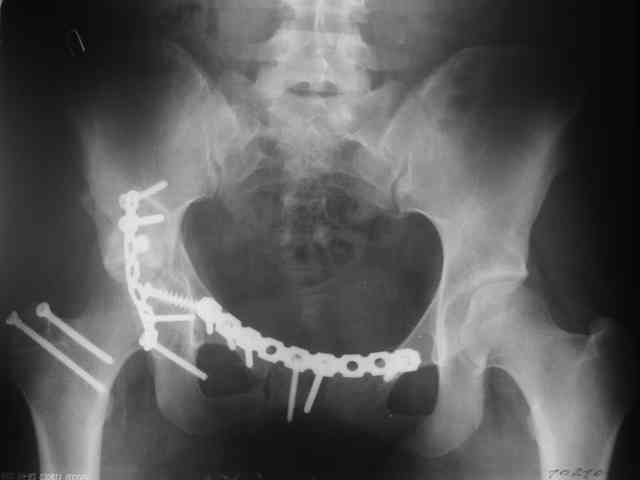

P.S. в приложении R пациентки с похожей проблемой доступа.. за исключением того, что перелом

двухколонный. Вертлугу лечили Y доступом.